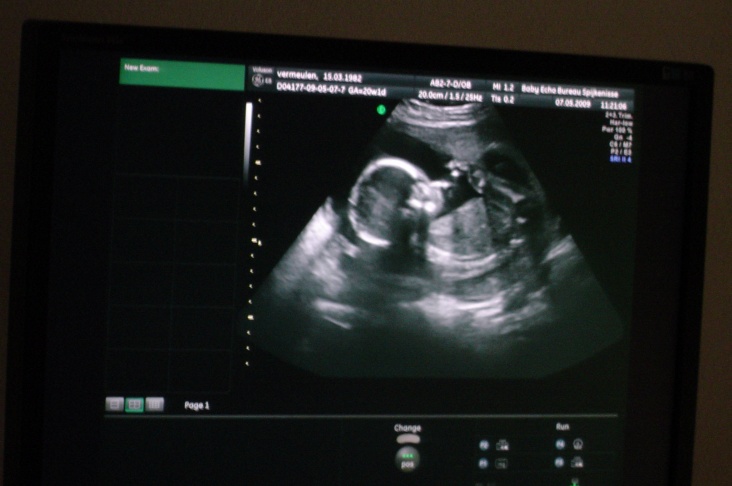

hierbij nog een paar foto's van de kleine in 4-d.

die rare vormen komen door de navelstreng ,de techniek is nog niet zover dat ie dat kan onderschijden van het lichaam, dus maakt ie er 1 geheel van.

met een beetje geluk bij 30 weken+ ook weer een fotootje.